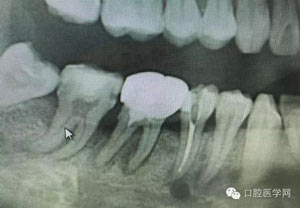

病例1:患者迫切希望保留自己的這一顆牙齒,根尖周陰影比較大,二度松動.而且旁邊有種植修復(fù)體,和患者溝通好后,治療好后觀察一個月后冠修復(fù),因為有種植的后期修復(fù),所以有了機會觀察,術(shù)后三個月和術(shù)后四個月,根尖恢復(fù)的還算不錯,希望能夠繼續(xù)觀察下去.這樣子的病例,做的時候我們一定要非常的小心,和患者要有充分的溝通以及不同科室的溝通然后決定怎么樣做比較好,假如就是出現(xiàn)了問題,到時候我們也比較好處理些,免得我們自己到時候不好收場。